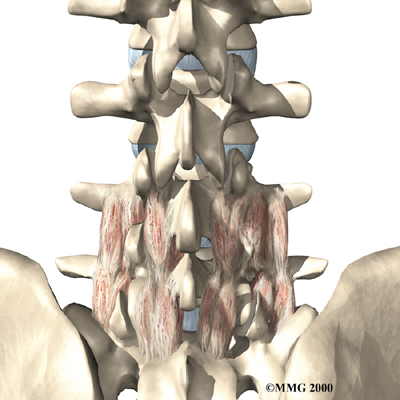

Posterior Lumbar Fusion

Lumbar disc herniation causes mechanical pain, the type of pain caused by wear and tear in the parts of the lumbar spine. Fusion surgery is mainly used to stop movement of the painful area by joining two or more vertebrae into one solid bone. This keeps the bones and joints from moving, easing mechanical pain.

In posterior lumbar fusion, the surgeon lays small grafts of bone over the problem area on the back of the spinal column. Most surgeons will also apply metal plates and screws to prevent the problem vertebrae from moving. This protects the graft so it can heal better and faster.

Related Document: FYZICAL Bridgeville's Guide to Posterior Lumbar Fusion